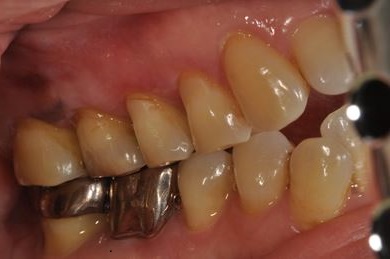

インプラントの症例写真 IMPLANT

インプラント治療+ソケットリフト+GBR

| 性別/年齢 | 女性 / 55歳 | ||||||||||||||||||||||||||||||||

| 主訴 | 奥歯が3本抜歯されてしまったあとにインプラントを入れたい。 | ||||||||||||||||||||||||||||||||

| 治療内容 | インプラント3本(ソケットリフト、GBR)、ハイブリッドセラミック3本 | ||||||||||||||||||||||||||||||||

| 総治療費 | 1,295,300円 | ||||||||||||||||||||||||||||||||

| 治療期間 | 8ヶ月 |